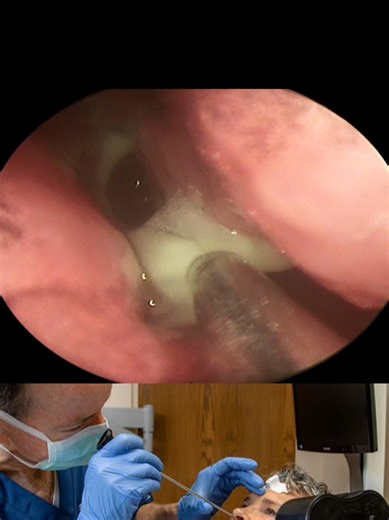

Endoscopic Sinus Surgery: Ten R